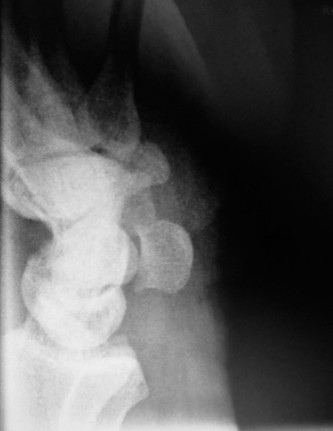

CASE 1 A 63-year-old male sustained a hyperextension injury to his neck while diving into a pool. Upon presen…